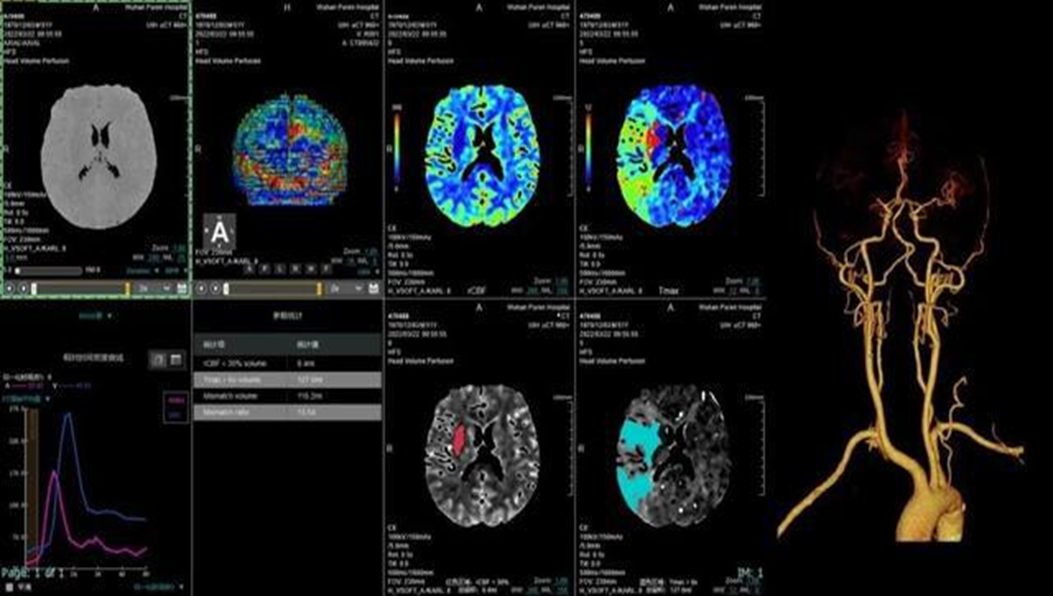

脑卒中中心

具备业内最便捷脑卒中解决方案,4D动态一站式卒中解决方案;一次对比剂注射即可获取脑动脉、脑静脉血管成像、CT灌注成像和 4D动态图像,助力脑卒中解决方案。使检查时间最短化,图像评估直观化,为抢救生命争分夺秒。

4D动态一站式卒中解决方案

颈脑动脉CTA+CTP